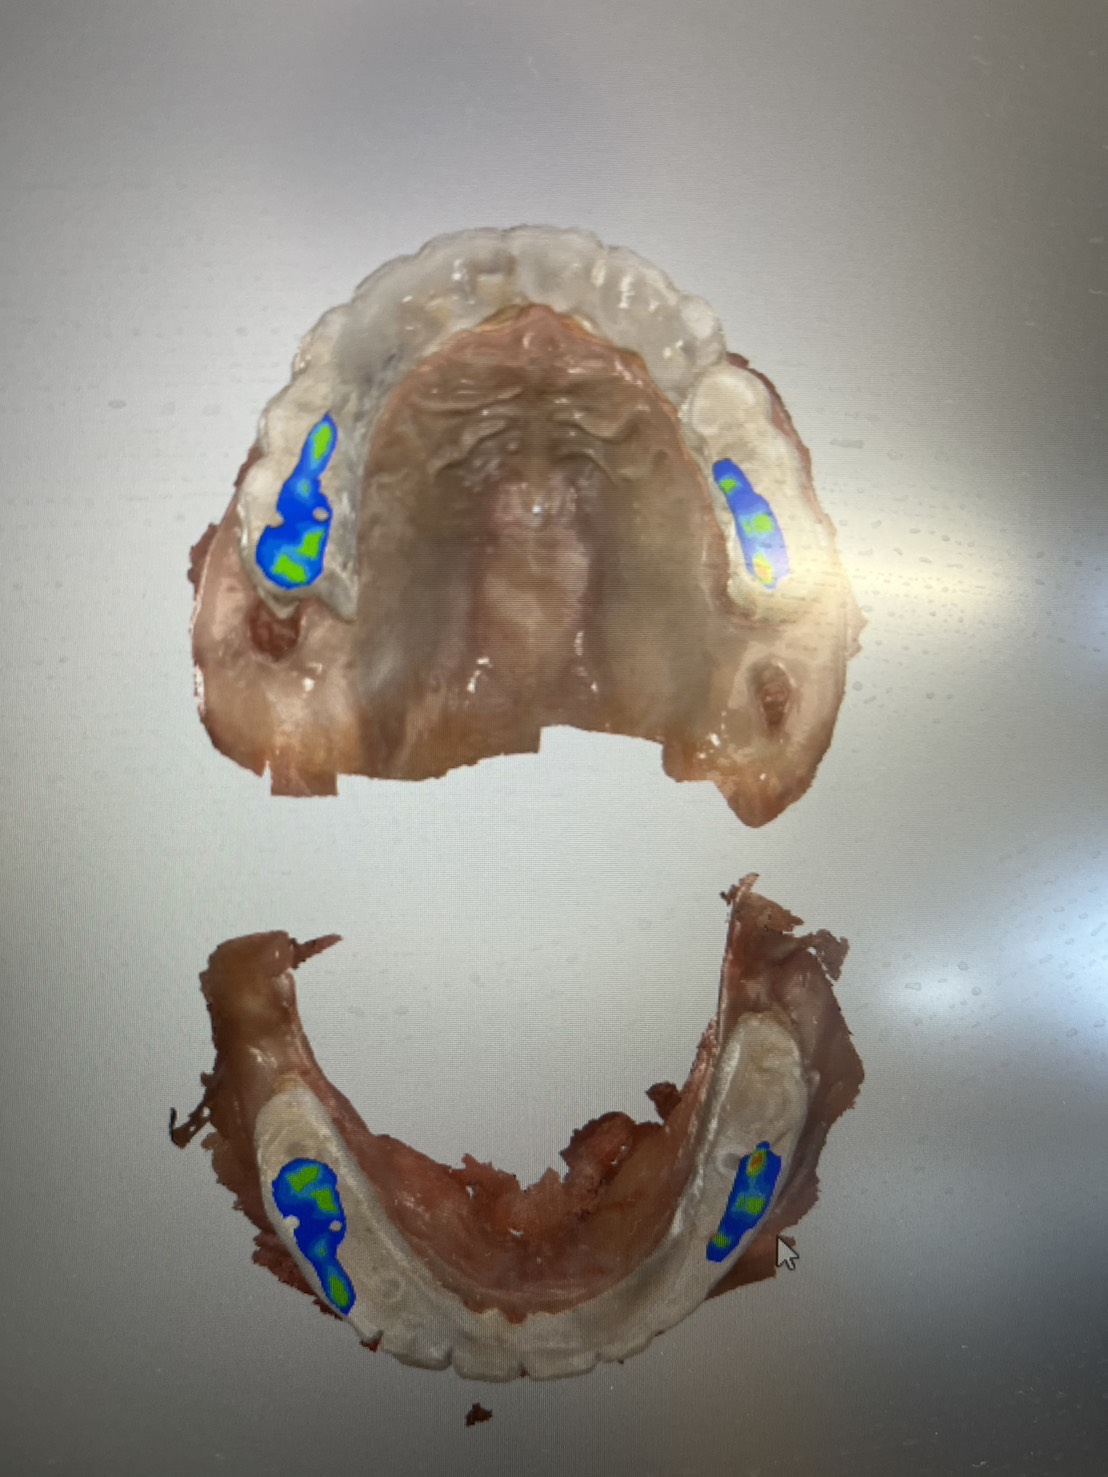

一位患者特地從外州飛到拉斯維加斯,評估後當天決定進行全口植牙。整個療程不到兩小時,即拔即植即固定臨時牙。

手術當天完成全口掃描,四個月後更換為最終固定假牙。這段期間,患者維持良好的生活品質,醫師也能安心照護,不用每天提心吊膽、接不完病患來電。

不需要全身麻醉,或者是舒眠麻醉的情況之下,就完成與自然牙排列相仿全口重建。不用擔心歪斜長長的植體打到顴骨或眼睛。

精奈創:最安全、最有效率的植牙技術,醫師患者都很安心。